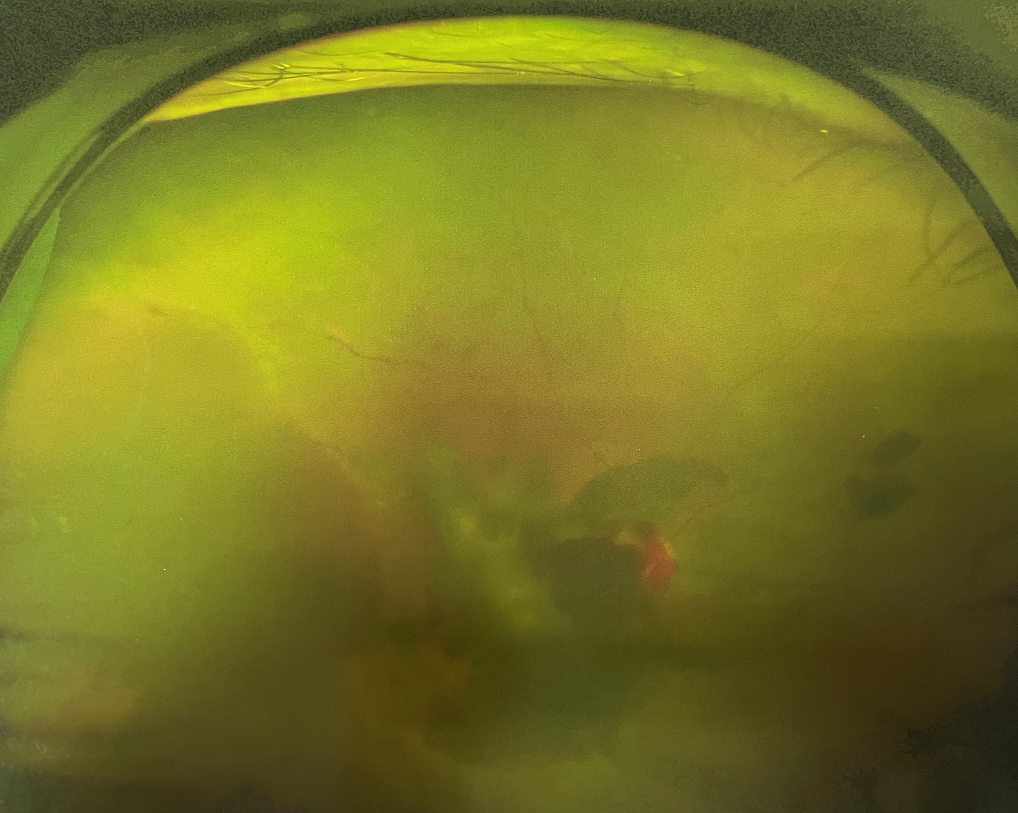

眼底出血不是獨立的眼病,而是由于眼球自己的病變和某些全身疾病的并發(fā)癥導(dǎo)致眼底的視網(wǎng)膜或脈絡(luò)膜出血,如果出血量大就會進入到眼球的玻璃體內(nèi),從而影響視力,如果沒有得到恰當(dāng)?shù)闹委熆蓭砀鼑?yán)重的并發(fā)癥造成失明。

眼底出血的患者,如果出血量少,而且在視網(wǎng)膜周邊部可能沒有明顯癥狀,患者僅感到眼前有黑影浮動;如出血量多,將嚴(yán)重影響視力,甚至完全被黑影所遮擋僅剩光感;如出血位于視網(wǎng)膜的黃斑區(qū),患者視野中心區(qū)被暗影遮擋,周邊尚有部分視力。

先是散瞳檢查眼底,可以明確眼底出血的性質(zhì),出血部位和出血量有多少。眼B超檢查,對于眼底出血量特別多,無法看清眼底的患者,就需要進行眼部B超檢查,以了解出血量,出血部位、有無合并視網(wǎng)膜脫離;還可以明確是否患有視網(wǎng)膜或脈絡(luò)膜的腫瘤。